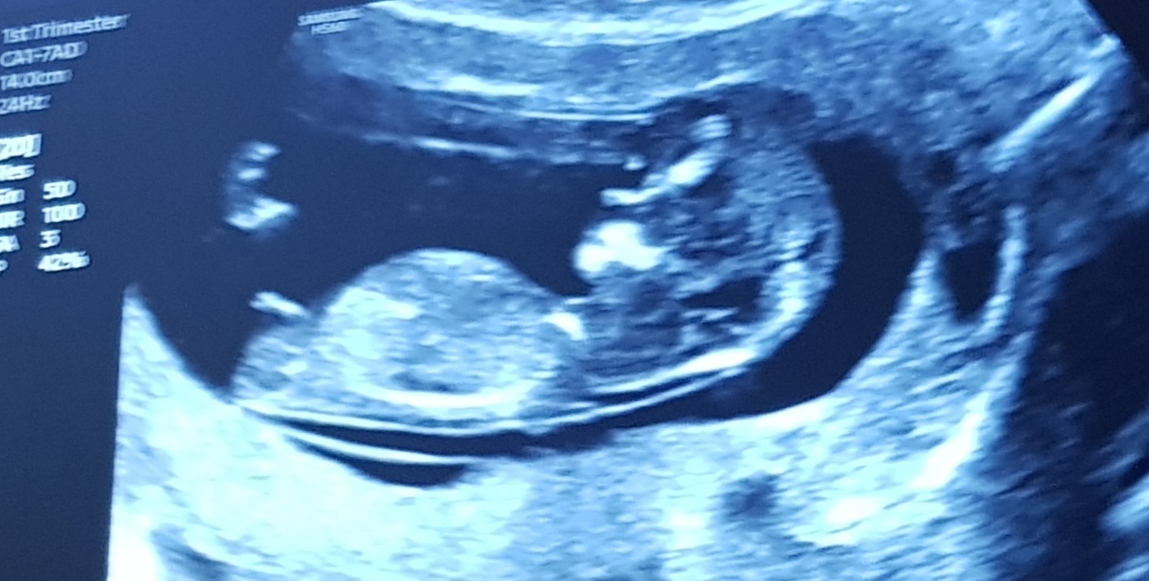

Scan at 12+2

A tad early for guesses but tentatively leaning boy. It could just be the angle though.

Leaning boy but I agree with ksmom in that the scan angle could be making the nub appear more angled than it actually is.

Thankyou for your reply and being so observant! I had a sacn at 11+2 and the nub looked alot more flat and girly but i didnt even think about angle in this one!i will upload those images for you love to hear what you think.xxx